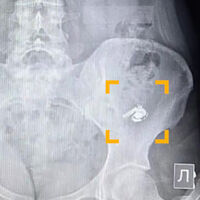

По словам уфимки по имени Мария, в момент глотания она почувствовала дискомфорт, но решила, что ей попалась крупная таблетка. Позже, обнаружив пропажу одного из наушников, девушка обратилась за медицинской помощью. В больнице ей сделали рентген, который подтвердил наличие инородного предмета в желудке.